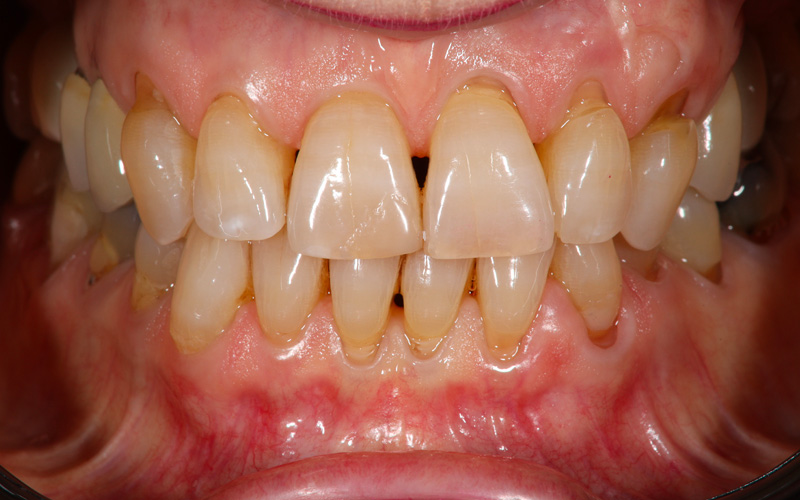

Nell'ultimo anno le è stata riscontrata complicanza a carico dei tessuti peri-implantari di elemento zona 25. L'esame visivo e lo status fotografico (Figs. 1-2) evidenziano un’alterazione dello stato dei tessuti molli peri-implantari, che guida il clinico verso un’indagine più approfondita tramite acquisizione RX. Si esegue perciò esame radiografico del sito coinvolto (Fig. 3), da cui risulta un’importante riassorbimento osseo a carico dell’impianto. Si procede con sondaggio peri-implantare profondo, con la finalità di definire estensione e forma del difetto (Fig. 4) e, associandolo all’esame radiografico, di eseguire la conta delle spire implantari esposte. Tale manovra verrà effettuata con l’impiego di anestetico da irrigazione, data la nota dolorolabilità in peri-implantite, in quanto tale patologia determina la perdita di barriere connettivali e pertanto la penetrazione in osso durante il sondaggio.

fotografia frontale baseline

Fig. 1 - Fotografia frontale al baseline che mostra una situazione generale di sufficiente controllo degli indici infiammatori.